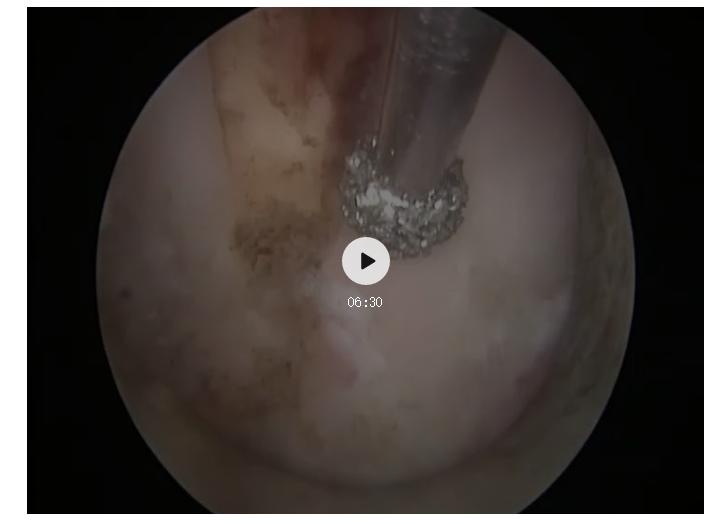

磨钻开窗

摘除髓核

探查手术结束

经过充分准备,一周后马主任带领手术团队为患者做了颈椎后路经皮内镜下颈椎间盘髓核摘除术。手术过程十分顺利,仅用时45分钟,且手术切口很小,约8毫米。